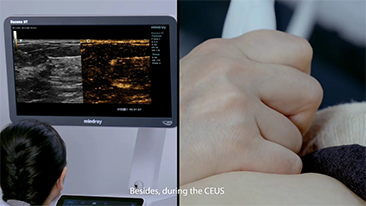

Le soluzioni Mindray Resona per la diagnostica per immagini generale consentono ai medici di ottenere diagnosi e trattamenti con risultati pi├╣ precisi ed efficaci grazie a sonde specifiche complete e a efficienti strumenti clinici applicativi.